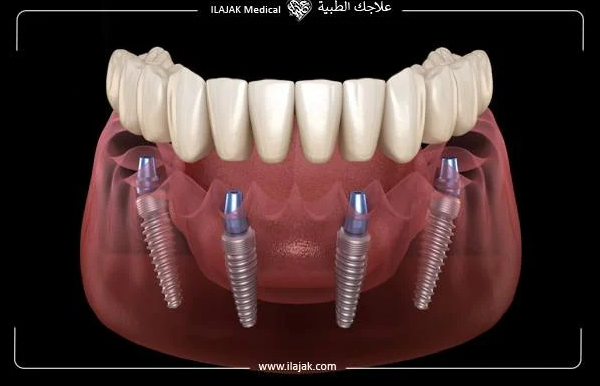

03. ALL-ON-4,6 임플란트

올온포 혹은 올온식스 형식의 임플란트도 있습니다. 위턱 혹은 아래턱에 4개 혹은 6개씩의 임플란트를 식립한 다음, 보철물을 고정하는 방식인데요.

어떻게보면 틀니랑 비슷하다고 보실 수 있지만, 엄연히 다른게 틀니는 탈착이 가능합니다. 하지만 올온포 형식은 탈착이 아닌 고정방식이기 때문에 탈착이 불가능합니다.

그래서 비용적으로 저렴하고 빠르게 적용해서 일상생활에 복귀할 수 있으나 관리적인 측면의 아쉬움이 있으며, 만약 문제가 생기면 보철물 자체를 변경해야한다는 단점도 있습니다.

하지만 실제 부산대학병원의 연구진들에 따르면, 올온포 방식은 골이식 없이도 가능하며, 하루만에 치아 회복이 가능하고, 1년 이상의 유지 관찰에도 높은 안전성을 보여 많은 환자들이 진행하고 있다고 하네요 (출처)